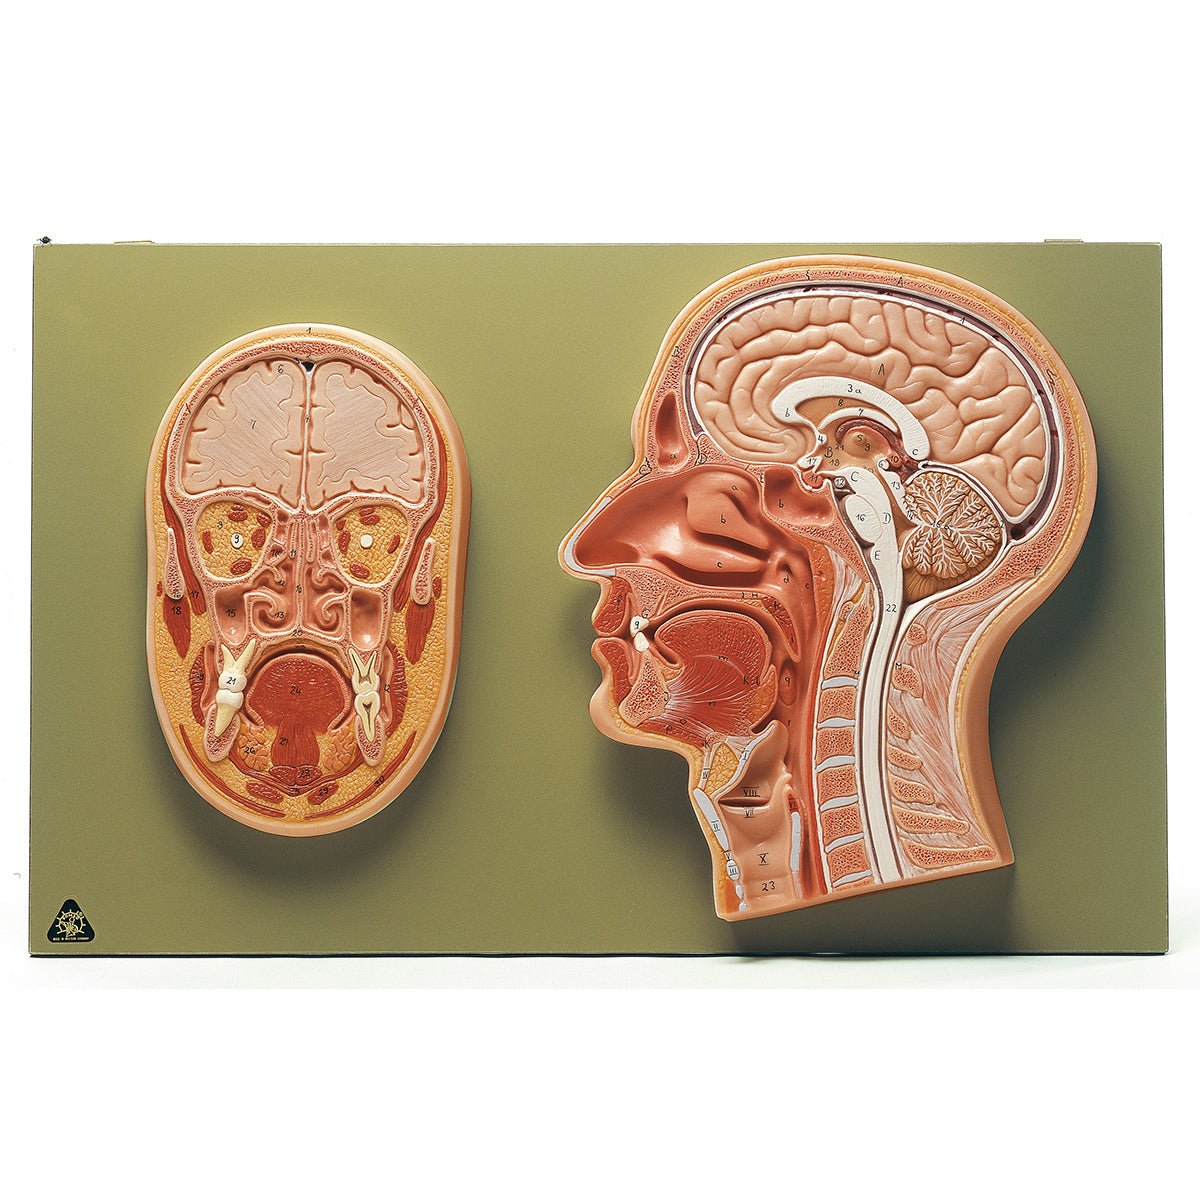

Base of the Head (BS 5/1) · Anatomy models | SOMSO®。Somso Base of the Head, Anatomical Model。Somso Median Section of the Head, Anatomical Model。あやや。SOMSO Anatomical Section Of The Head with MRI Imaging。。写真のように細かなパーツにまで分解できます。Somso Head with Muscles, Anatomical Model。欲しい方はコメントください。SOMSO Nerves and Blood-Vessels on the facial Skull。SOMSO Model of the Head Anatomy Model | Anatomy Warehouse。somso-head-and-neck-model-bs3-。大脳鎌付きの頭部模型です。Model of the Head | Nerves / Blood-Vessels | Head / Neck。SOMSO Half of the Head – GTSimulators.com。リアリティのあるものが欲しい方は是非。ちなみに、ヒト頭部骨標本(本物: 下顎、歯牙も全て揃っています)もあります。SOMSO Model of the Head - Natural size – GTSimulators.com。SOMSO 14-Piece Model of the Skull – GTSimulators.com。本物で頭蓋底などを勉強したい人にお譲りします。(価格は安くはありませんが、、)